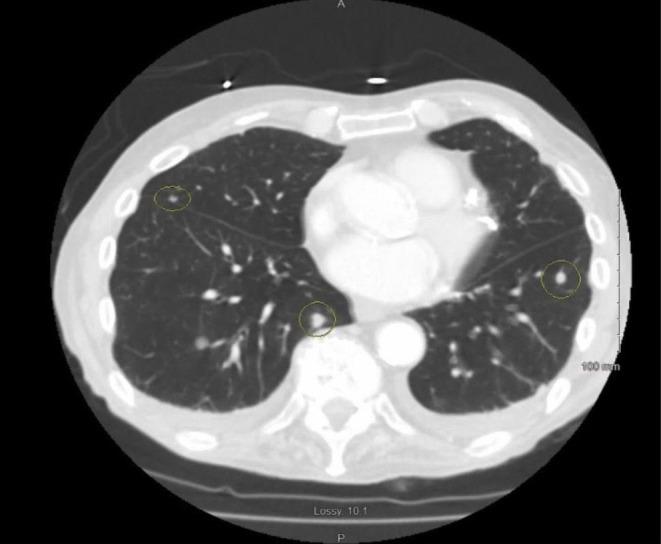

疑似舌部转移性平滑肌肉瘤所致副肿瘤性运动障碍:一例报告

Paraneoplastic movement disorder due to suspected metastatic Leiomyosarcoma of tongue: A case report.

Paraneoplastic movement disorders, though rare, can be the initial symptoms of malignancies like leiomyosarcoma, as in our case. Clinicians should keep malignancies in their differential diagnosis in cases of unexplained movement abnormalities.

摘要